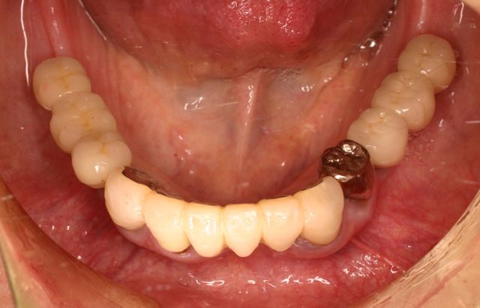

術後、左下奥2本インプラント(鏡像)